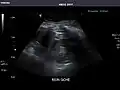

Kidneys: Right and left kidneys measure 11.5 cm and 12 cm in length respectively. No hydronephrosis. Small left lower pole kidney cyst.

Right kidney -